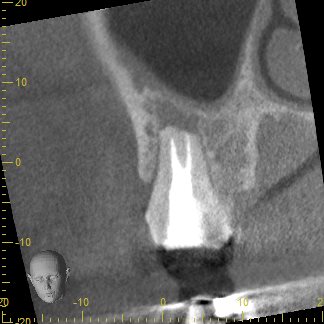

歯根周囲の骨の吸収が大きく、保存が可能かどうか判断が難しいと思われたCT画像

従来のレントゲン画像は全てのものが影絵として一枚の平面に写し出されるため、根の先の病巣の大きさを詳しく調べることが困難です。そこで、CT撮影を行うことで、3次元的に様々な角度で確認し、根の先の病巣がどれほどの大きさを調べその歯が保存可能なのかどうかを診ていきます。

この写真は術前のCT画像です。

歯根の周囲に見られる黒くなっている部分は、細菌の感染により骨が吸収しています。根尖病巣と呼ばれるこの部分が大きいほど治る確率が下がると言われ、根管内の細菌数も多いことがほとんどです。

ここまでの吸収があると、歯根が破折してる可能性を考える必要があります。